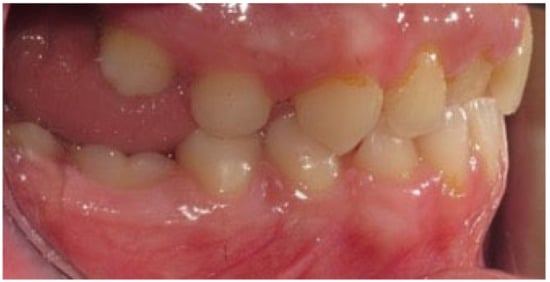

Figure 5.

Right photo of the female patient with PFE in bite relationship.

Figure 6.

Left photo of the same female patient depicted in Figure 5.

Open bite is present at the right posterior segment due to the impaction of the upper and lower left first molars.

Figure 5 and Figure 6 present a PFE case of a 17-year-old female patient referred to the Orthodontic Clinic of the Dental School of the National and Kapodistrian University of Athens, Greece. Clinical examination showed a posterior open bite on the right segment, as well as infraoccluded left upper and lower first molars. The patient’s orthopantomography shows no visible PDL of the right upper and lower first molars or the teeth distally related to them.